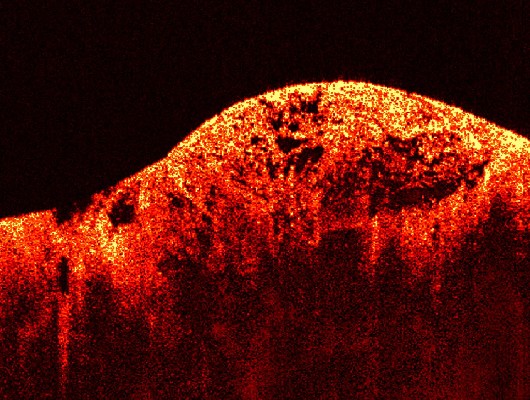

CHEMICAL DYES AS CONTRAST AGENTS FOR OPTICAL COHERENCE TOMOGRAPHYTech for Transfer TTO 17-01-2016 This invention utilizes chemical dye in optical coherence tomography (OCT) by altering the optical spectrum of incident radiation. Biophotonics Optical Imaging and Processing Tell me more |

MOLECULAR BIOMEDICAL ENGINEERINGTech for Transfer TTO 15-01-2016 Optical contrast agents and molecular detection technologies to enhance the ability of optical coherence tomography (OCT) to non-invasively map molecules in living specimens and diagnose disease. Biophotonics Nanophotonics Optical Imaging and Processing Plasmonics Tell me more |

GOLD NANOSTRUCTURES FOR OCT IMAGING OF BLOOD FLOWTech for Transfer Hidden author 23-09-2014 Plasmon resonance and low toxicity of gold nanoparticles enable their application both for diagnosis and treatment of cells and tissues. Gold Nanostars and nanostar-based nanocomposites owing to high electic field intensity at their tips are promising contrasts agents for optic coherence tomography OCT imaging. Nanophotonics PlasmonicsThis Listing is confidential. |